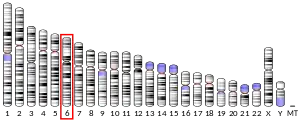

| Aliases | CGA, CG-ALPHA, FSHA, GPHA1, GPHa, HCG, LHA, TSHA, Chorionic gonadotropin alpha, glycoprotein hormones, alpha polypeptide, Alpha subunit of glycoprotein hormones, GPA1 | ||||||||||||||||||||||||||||||||||||||||||||||||||

| External IDs | OMIM: 118850 MGI: 88390 HomoloGene: 587 GeneCards: CGA | ||||||||||||||||||||||||||||||||||||||||||||||||||

Glycoprotein hormones, alpha polypeptide is a protein that in humans is encoded by the CGA gene.[5]

The gonadotropin hormones, human chorionic gonadotropin (hCG), luteinizing hormone (LH), follicle-stimulating hormone (FSH), and thyroid-stimulating hormone (TSH) are heterodimers consisting of alpha and beta subunits (also called chains) that are associated non-covalently. The alpha subunits of these four human glycoprotein hormones are identical; however, their beta chains are unique and confer biological specificity. The protein encoded by this gene is the alpha subunit and belongs to the glycoprotein hormones alpha chain family.[6]